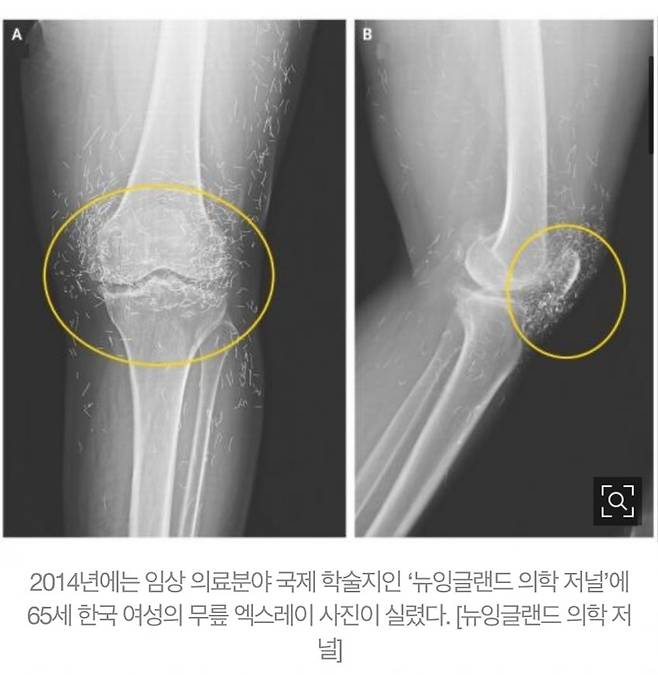

예전에는 무자격자 침술사들이 금침요법이라고 몰래 몰래 하던걸 요즘은 산부인과나 성형외과에서 금실 리프팅이란 이름으로 미용목적으로 한디고 ㅋㅋㅋ

해외 학술지에도 올라간 금실 박힌 엑스레이 사진